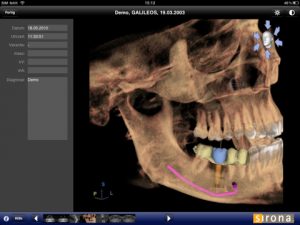

Our office uses the 3D Guided Implant Surgery technology: The Sirona XG-3D Cone Beam Cat Scan System for 3D implant placement along with the Sicat Guide system.

Using 3D X-Rays and a combination of regular and 3D impressions we get a perfect picture of your bone, teeth and jaw. The software “stitches” the X-Ray to the models and creates a full digital representation of the jaw. Using this precision digital model, we can experiment with different implant sizes and designs and perfect the angles of your implants. We can even plan the type of restoration we will be making for you. After all, the end goal is a new tooth – not just an implant. This produces the highest quality results in the safest and most predictable manner possible.